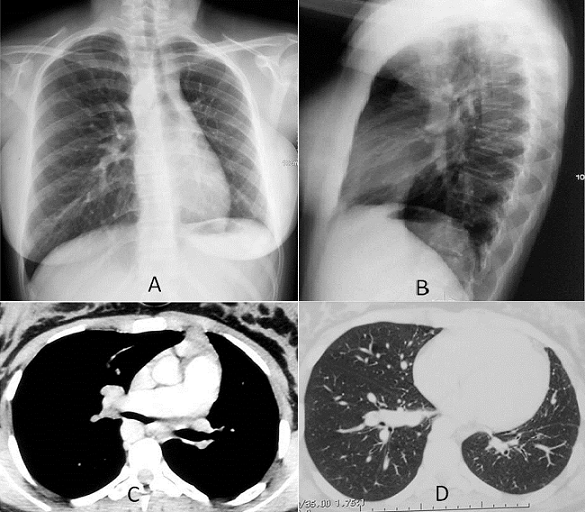

L’agénésie unilatérale de l’artère pulmonaire est une malformation rare concernant 1% des cardiopathies congénitales et qui peut être source de plusieurs complications. Nous rapportons le cas d’une jeune patiente âgée de 16 ans, sans antécédents pathologiques, présentant une hémoptysie de faible abondance récidivante dans un contexte de conservation de l’état général. L’examen clinique est sans anomalie et la radiographie thoracique de face (A) et de latéral (B) montre un aspect de petit champ pulmonaire gauche, une diminution de la trame vasculaire avec déviation du médiastin à gauche. Devant ce tableau radio-clinique on a évoqué une hypoplasie pulmonaire gauche, séquelles d’infection pulmonaire anciennes ou un corps étranger endobronchique. L’angioscanner thoracique objective l’absence de l’artère pulmonaire gauche (C) avec de nombreuses collatérales systémiques. Le parenchyme pulmonaire gauche est hypoplasique, bien aéré et sans anomalie bronchique (D). À noter que l’aorte descendante est située à droite. L’électrocardiogramme montre un aspect de bloc de branche droit et l’échographie trans-thoracique ne trouve pas d’anomalie cardiaque notamment pas de signe d’hypertension artérielle pulmonaire. La fonction respiratoire à la spiromètrie est normale ainsi que les examens biologiques. L’hémoptysie a été contrôlée par traitement symptomatique et la patiente est sous surveillance médicale.